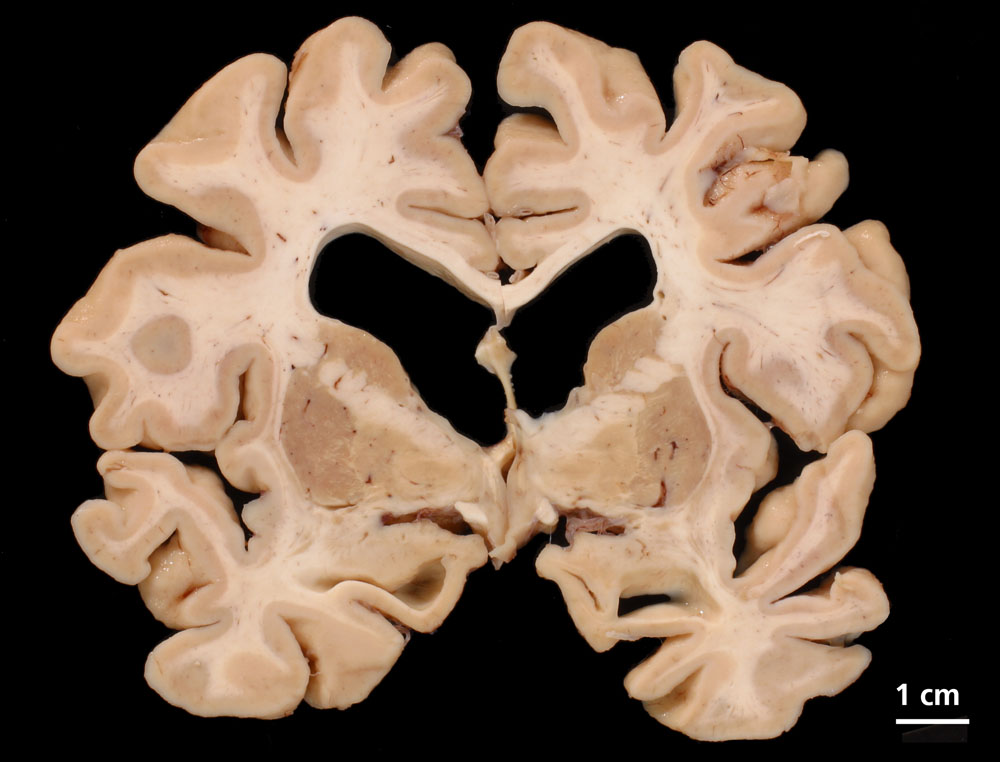

Die Grosshirnhemisphären stellen sich symmetrisch dar und zeigen eine ausgeprägte kortikale Atrophie. Zusätzlich zeigt der koronare Schnitt eine starke Erweiterung der inneren Liquorräume mit Abrundung der Seitenventrikel. Die Basalganglien sind unauffällig.

Morbus Alzheimer (sicherer Morbus Alzheimer gemäss CERAD, Stadium 2-3 nach Braak und Braak). Demenz mit Lewy-Körpern (DLB, limbischer Typ, laut Newcastle Kriterien). Amyloid-Angiopathie.